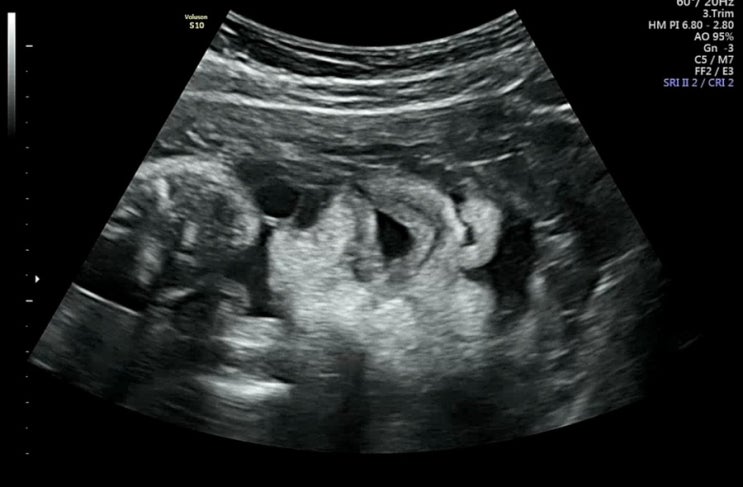

임신기록 31~32주 | 배뭉침 병원방문, 태아 몸무게 늘리기 성공?

31주차 증상 - 화장실 자주감 - 31주차 +10kg 돌파, 태아 몸무게 1.7kg 일주일만에 500g 살크업 성공 ? ...